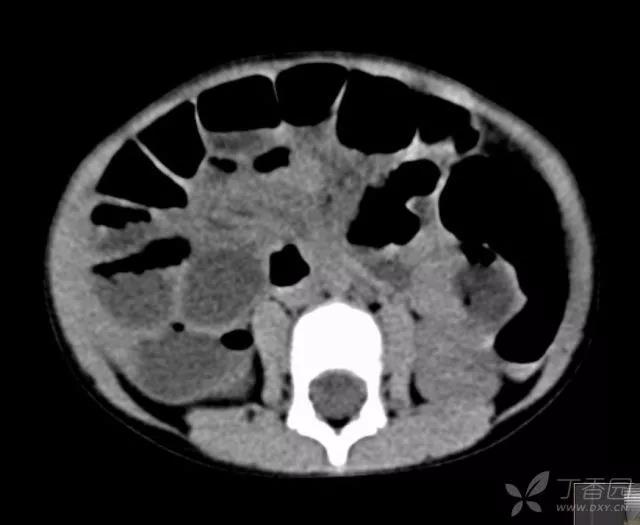

4岁,女童,3 天前开始腹痛,2 天前就诊当地医院,治疗后腹痛不缓解,X 片是小肠梗阻,建议至上级医院就诊。

至本院就诊时:精神萎靡,腹部拒按,经检查考虑急性阑尾炎穿孔并腹膜炎,予急诊手术。

小小的腹腔,胀胀的肠管,几乎没有操作空间,开腹手术似乎是最佳选择,要想冲洗腹腔干净,没有 6 cm 切口,几乎是不可能的。

儿童阑尾,通常合并腹膜炎和肠梗阻,空间小,阑尾难找或处理,可在操作情况下调节压力,由 9 上调至 12; 充分利用腔镜纱条,可以在小空间里处理阑尾。